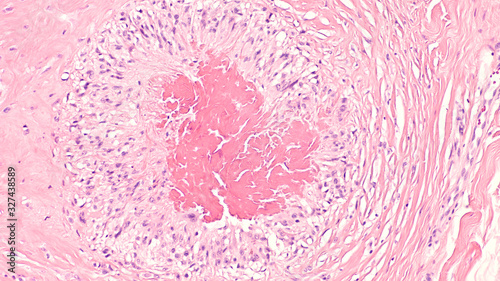

Mikrofotografi - Plakater, Poster, Billeder på lærred